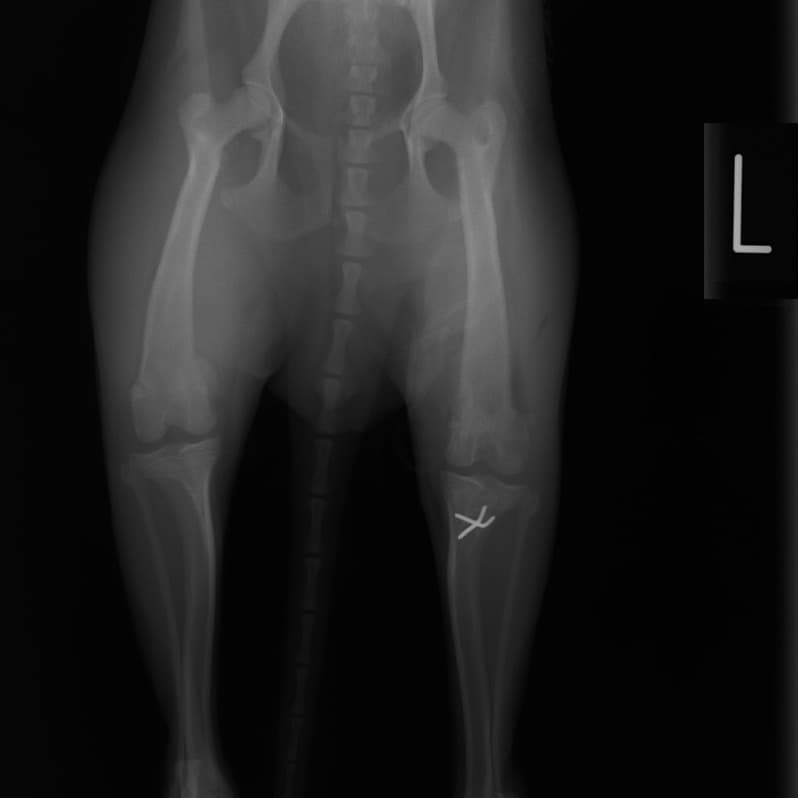

■ 症例24 キャバリア 7か月

左右膝蓋骨内方脱臼(左:グレードⅣ 右:グレードⅢ)

以前から左右後肢の跛行が認められ、整形外科学的検査・レントゲン検査により左右の膝蓋骨脱臼が認められた。症状が重度である左膝の膝蓋骨脱臼整復術を行った。外科手技は縫工筋及び内側広筋の解放、脛骨粗面の外側転位、滑車ブロック形造溝術、内外側関節方の縫縮を実施した。術後一か月時点で、左の膝蓋骨は安定しており経過は良好である。

本症例は成長期における重度の膝蓋骨脱臼であり、術後の再発の可能性もあるため、経過をしっかりと観察していく必要がある。また、今回手術を実施していない右膝に関しても経過を観察し、手術を検討していくこととする。